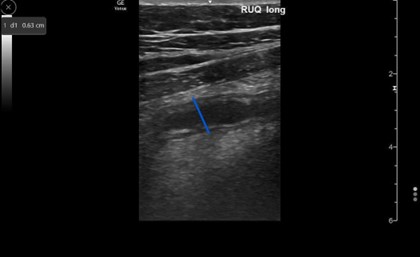

The appendix is most reliably found in the right lower quadrant; the base extends from the proximal cecum and lies anterior to the psoas muscle and the right iliac vessels. Most of the time the distal tip is retrocecal, though the challenge in localization is augmented as the appendix can be pelvically oriented (Images 5 and 6) or directed elsewhere in the abdomen. The normal appendix is tubular, non-peristalsing, compressible, and blind-ended, measuring less than 6 mm. (Image 7)

Image 7. Normal appendix, longitudinal view; appendix ending in blind pouch